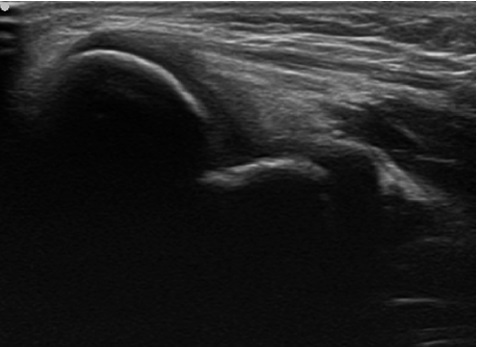

超音波観察では正常肘ではみられないような骨の不正像(↓)が認められました。

正常の肘のエコー画像

内側型野球肘のエコー画像